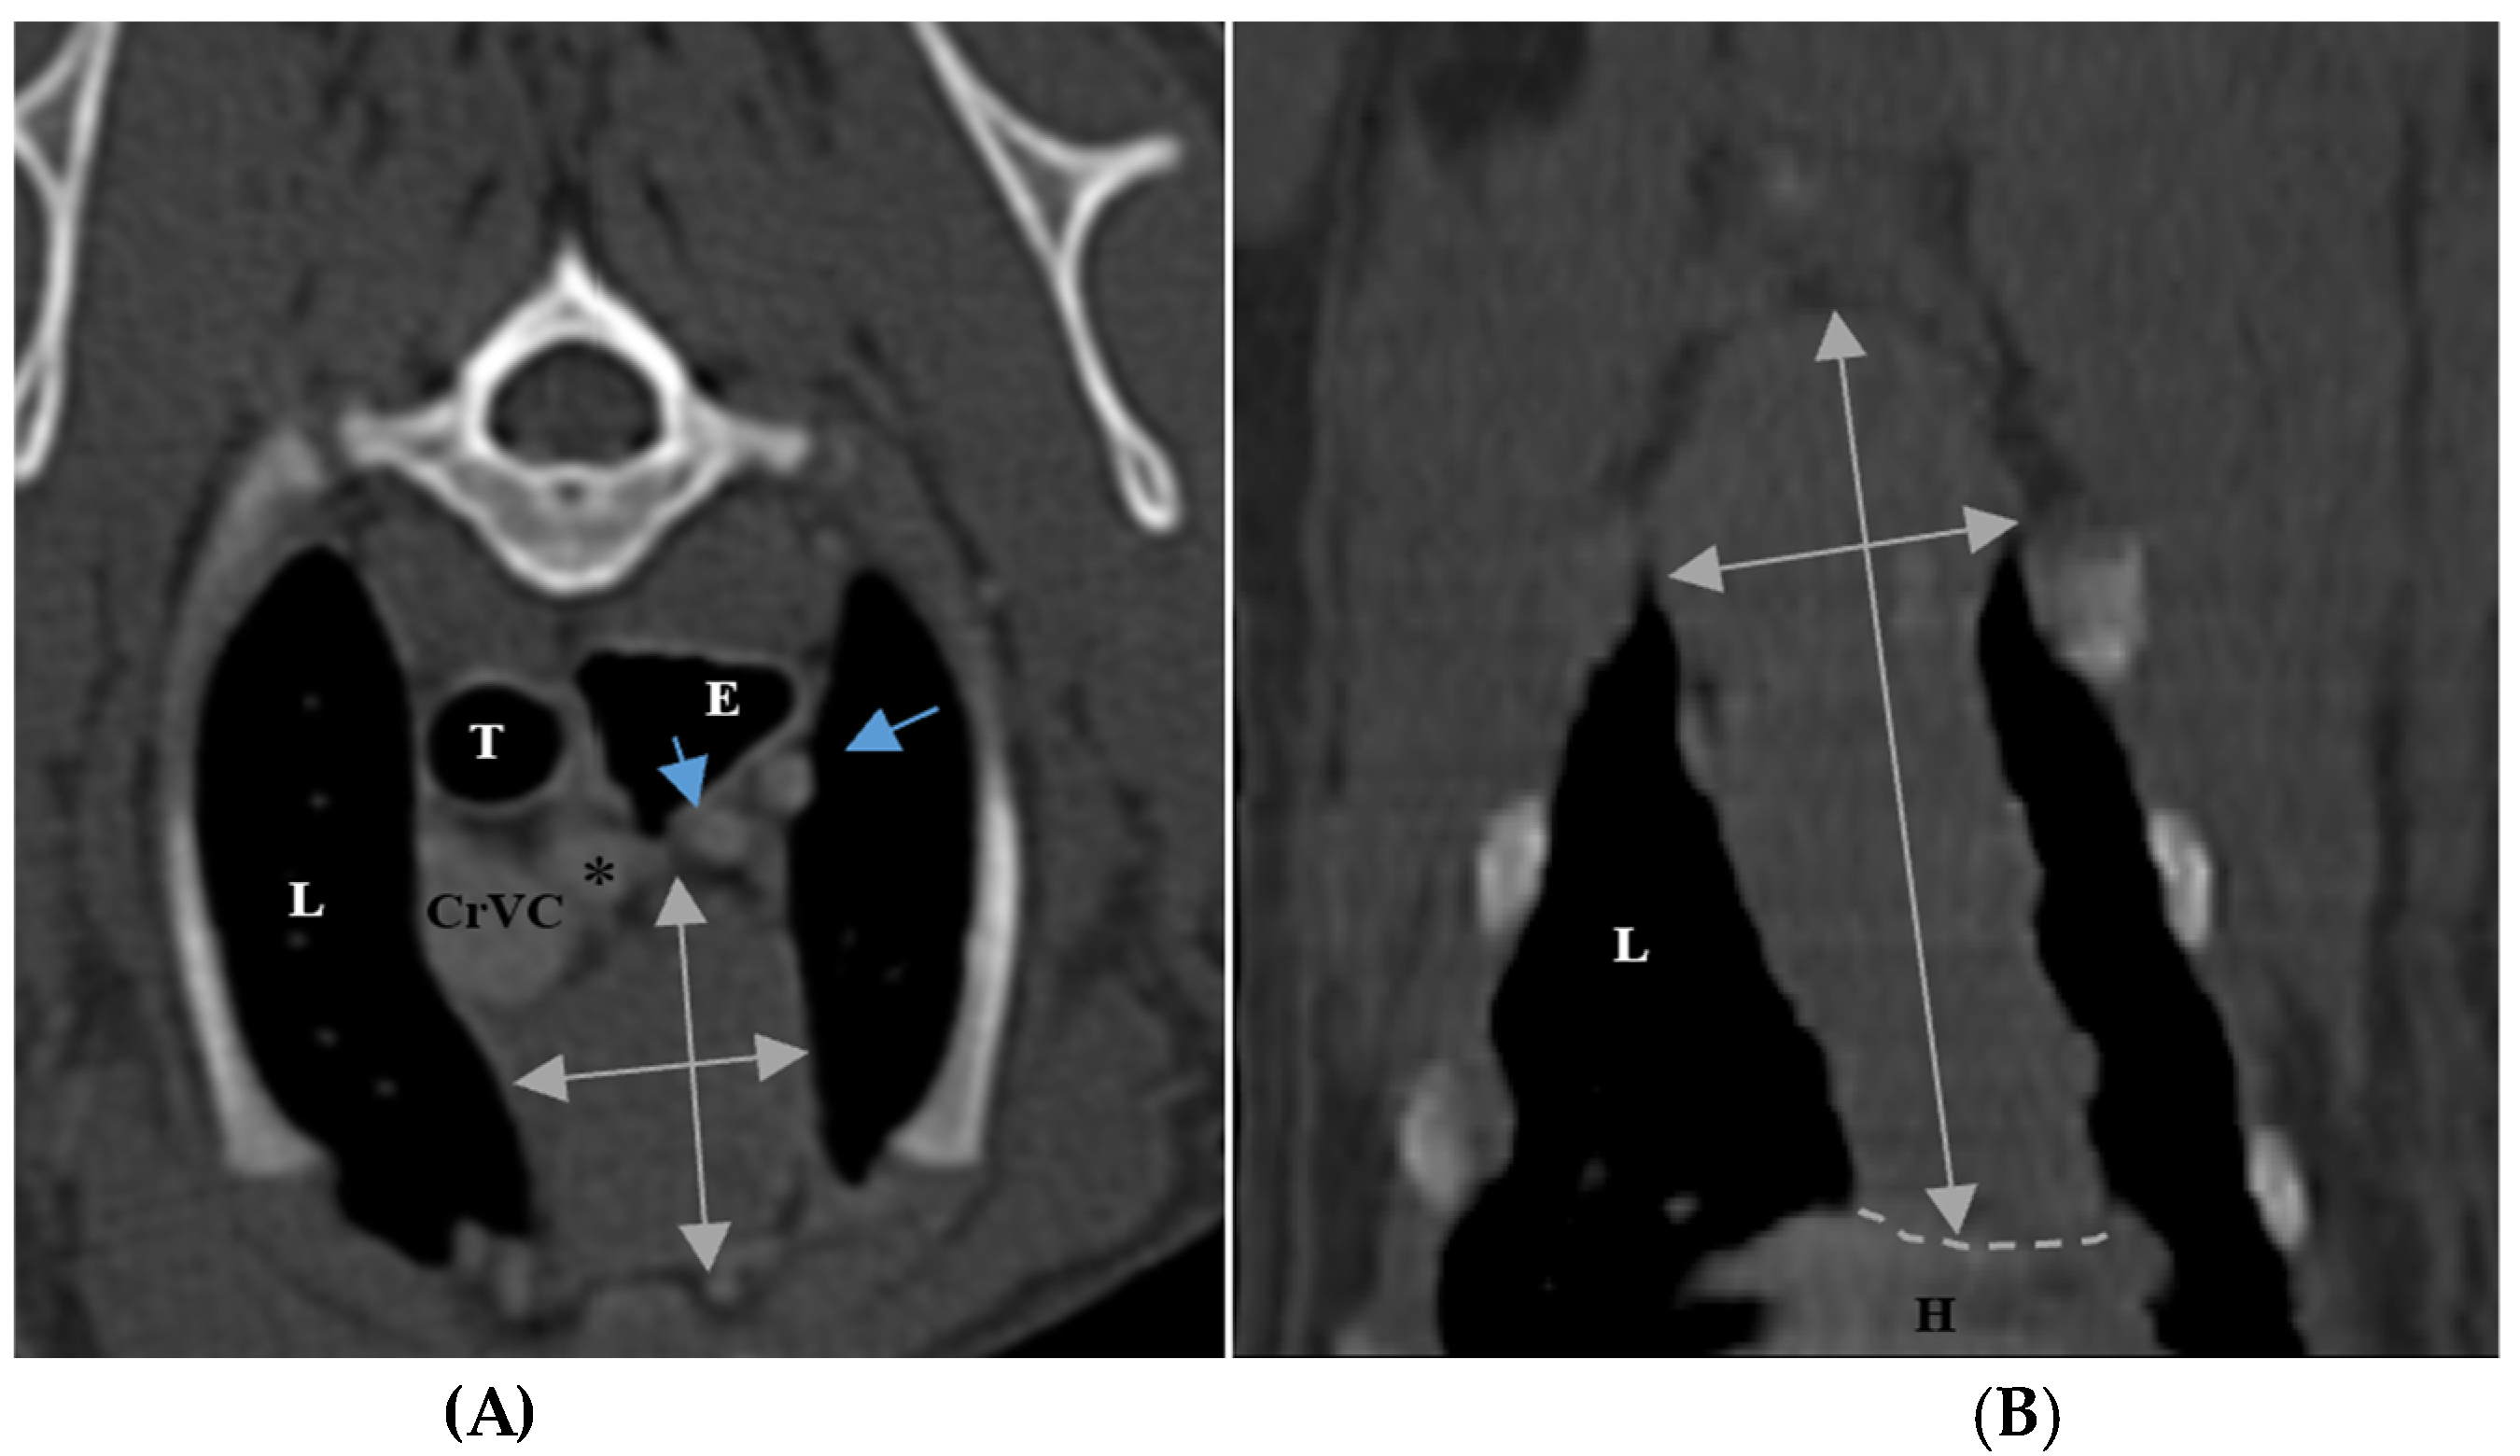

The size of the thymus was also measured in transverse and dorsal images. The maximum height (TH) and diameter (TD) in transverse images and maximum diameter (DD) and length (DL) in the dorsal views were measured (Figure 2), as well as thymic volume (TV) in all groups. These indices were measured in the area related to the mediastinal fat at the normal location of the thymus for patients with a completely fatty replacement of the thymus (grade 0). All measurements were performed in contrast-enhanced examinations. To normalize the thickness of the thymus in the transverse view, the height of the second thoracic vertebra midbody was measured and the ratio was calculated. The correlation between thymic size and grade with the body fat content was evaluated by measuring the thickness of subcutaneous fat in the dorsal aspect of the T4 spinous process (Figure 3). Subjective characteristics such as predominant deviation of the thymus to left, midline or right position, the thymic shape (wedge shaped, rectangular shaped, or linear shaped), and the thymic contour (convex and concave) were also evaluated. For patients with fatty degeneration, these characteristics were analyzed in mediastinal fat at the location of the previous thymus. Evaluation of thymic size, volume, attenuation, and grade was performed twice by a single person within a week, and the mean value of the first and second measurements for numerical data and the second results for thymic grading were reported.

Figure 2. Measurement of maximum height and diameter of thymus in transverse section (A) and maximum length and diameter in dorsal section (B) in post-contrast CT scans. The grey double arrows show the regions of measurement. Both figures belong to a five-month-old female shih Tzu. The thymus is grade 3, rectangular shaped with one convex border and midline position. L: lung, T: trachea, E: esophagus (which is dilated due to general anesthesia), CrVC: cranial vena cava, H: heart, black asterisk: right subclavian artery, shorter blue arrow: left common carotid artery, and longer blue arrow: left subclavian artery.